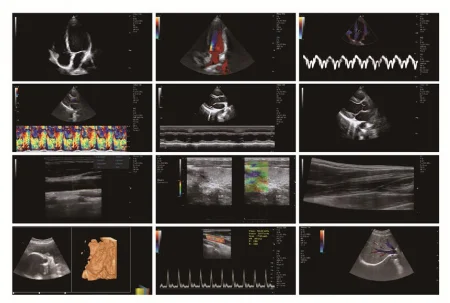

Product name | Medical Ultrasound Equipment |

Display | 15inch LCD display |

Probe | Convex,Linear,Vaginal,Rectal,Micro-convex |